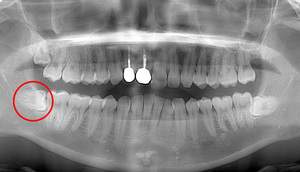

レントゲン写真

麻布十番歯科での右下の親知らずが真横に生えている症例のレントゲン写真

右下の親知らずが気になると言う主訴でいらっしゃった患者様です。

レントゲンで確認すると、真横にはえており、さらに、下歯槽神経と接触しているようにみえます。

根の形は先細りの形態ですので、抜くのはそこまで難しくないと思われます。根の形の最終確認と、下歯槽神経の位置確認のためにCTを撮影することにしました。